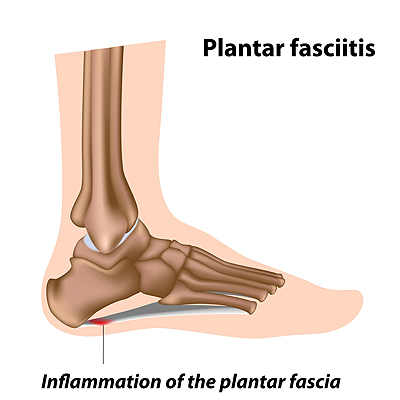

Can Other Foot Problems Cause Plantar Fasciitis?

Can Other Foot Problems Cause Plantar Fasciitis? Plantar fasciitis is a condition characterized by inflammation of the plantar fascia, a ligament that runs along the bottom of the foot and connects the toes to the heel bone. This ailment is characterized by a sharp,...